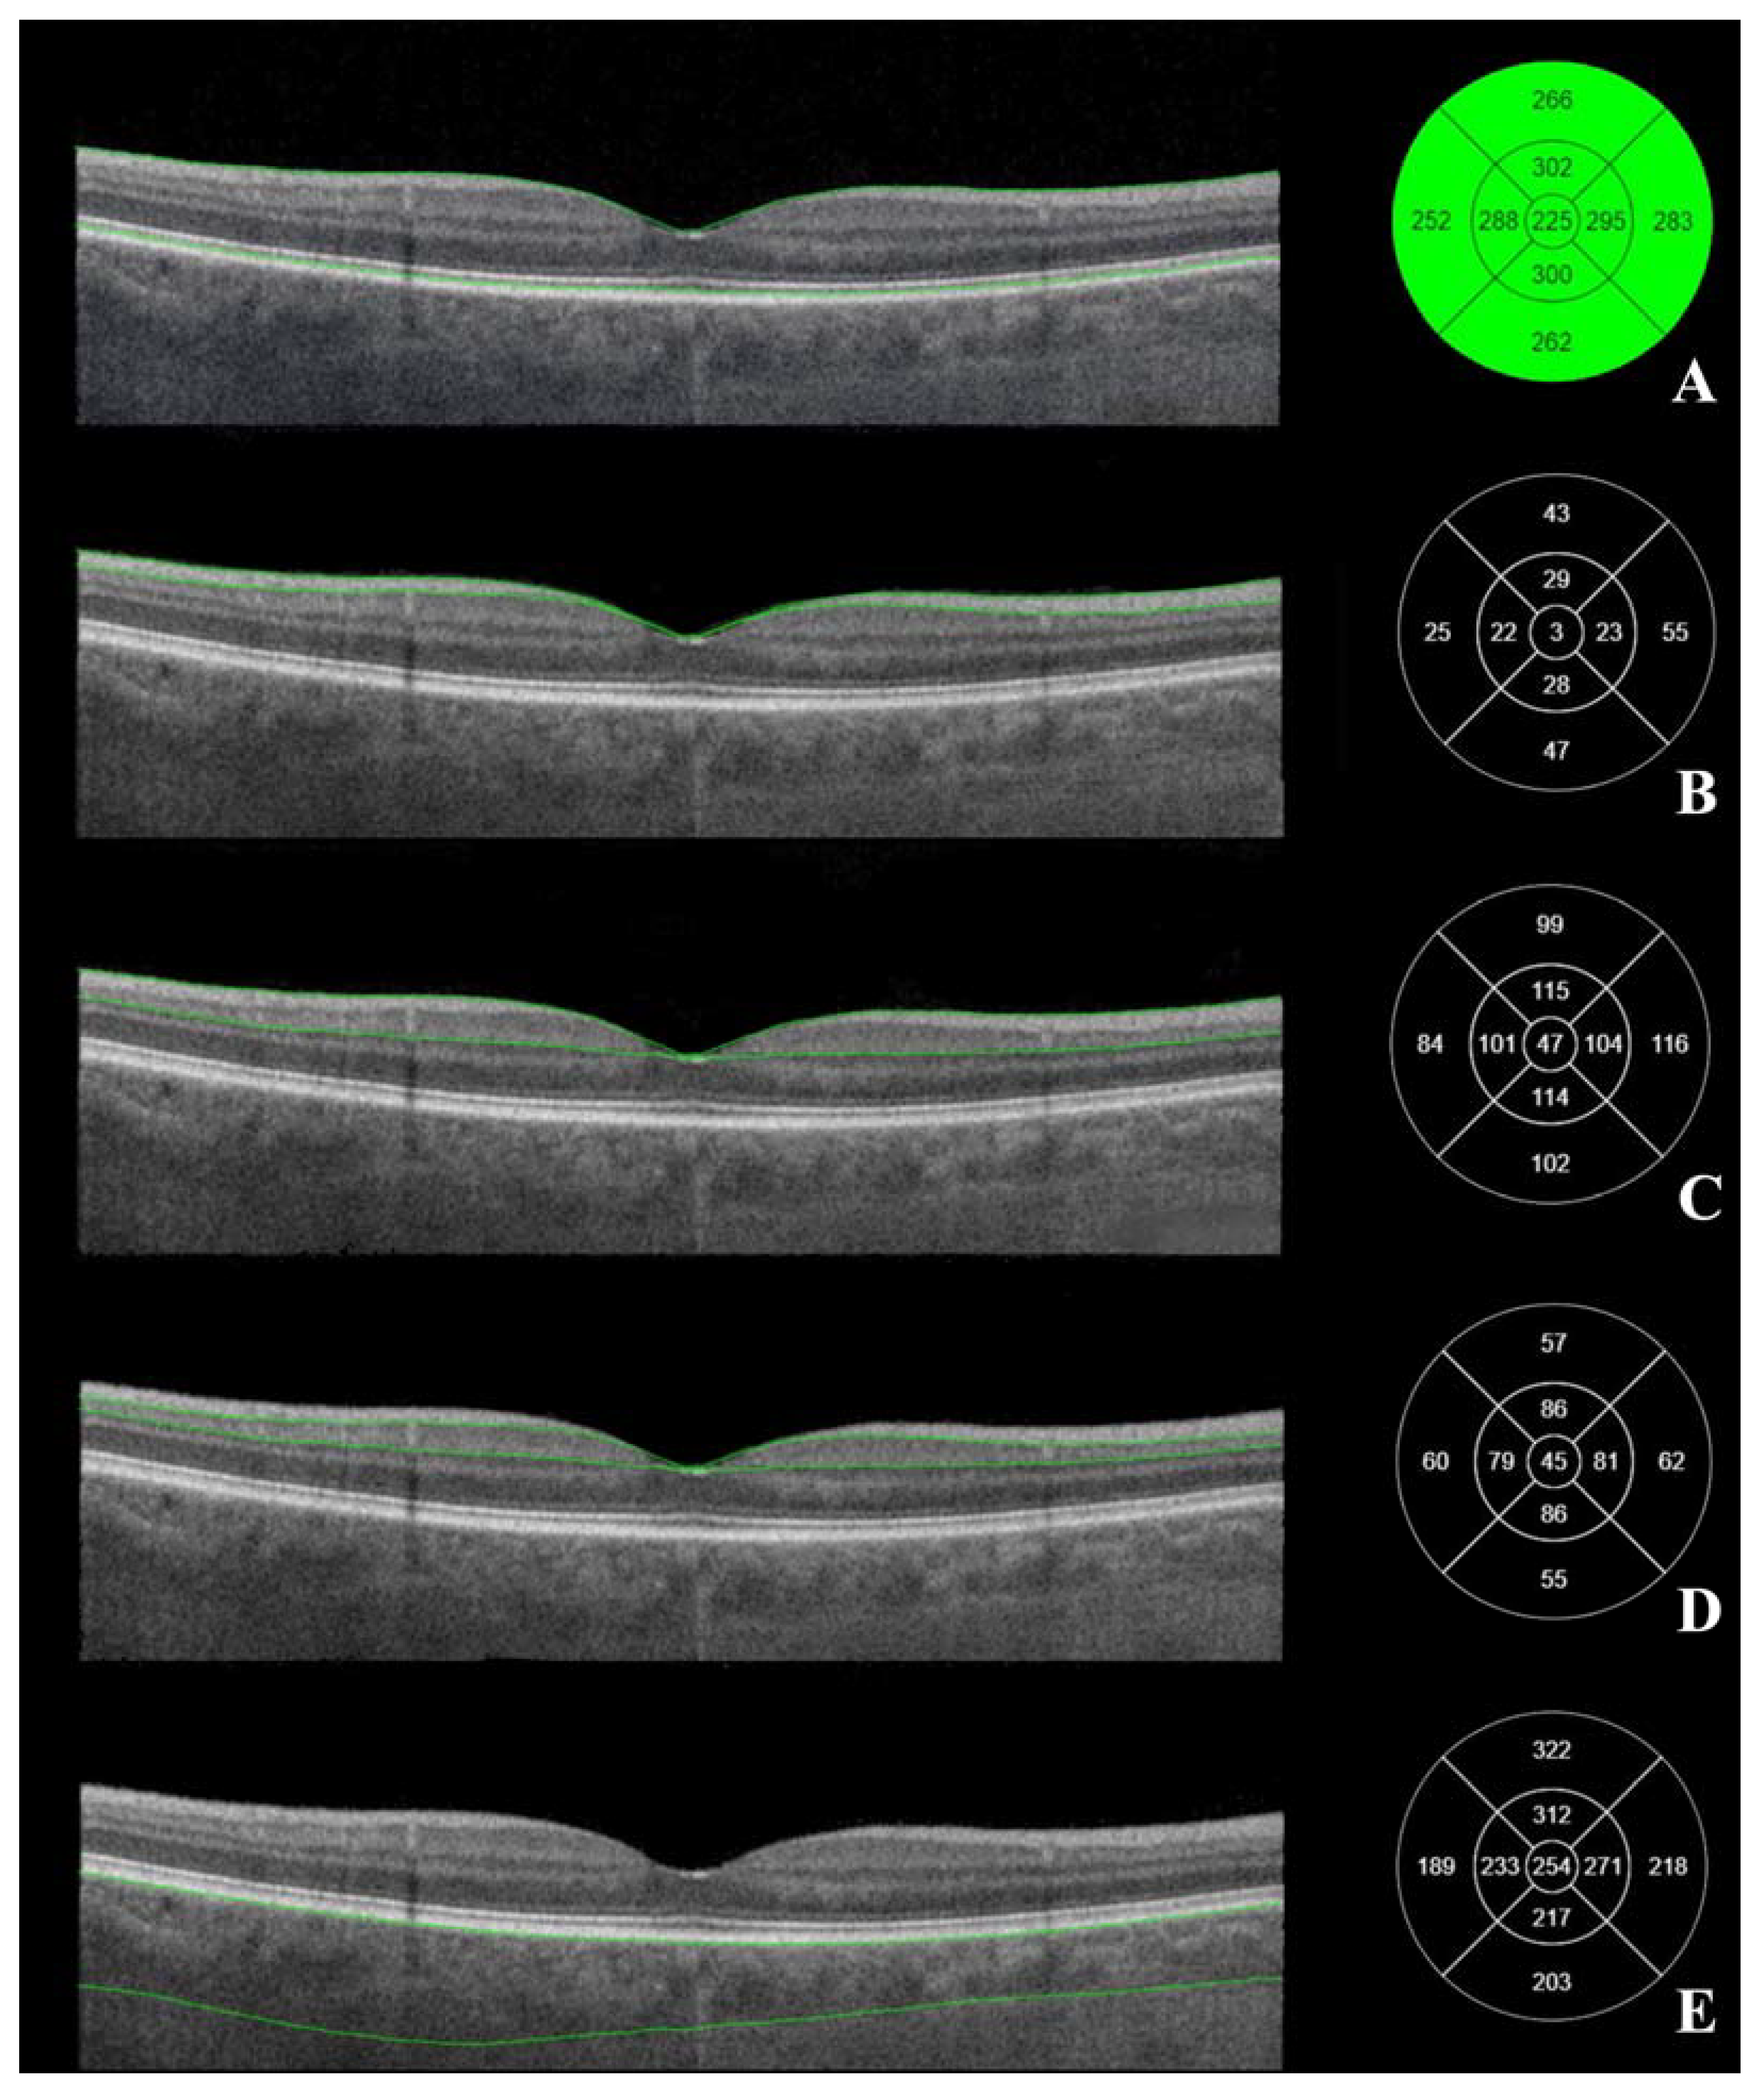

3.2. Posterior Segment OCT Results before the Cataract Surgery

3.3. Posterior Segment OCT Results Six Months after the Cataract Surgery

3.4. Comparison of Posterior Segment OCT Results before and Six Months after the Cataract Surgery